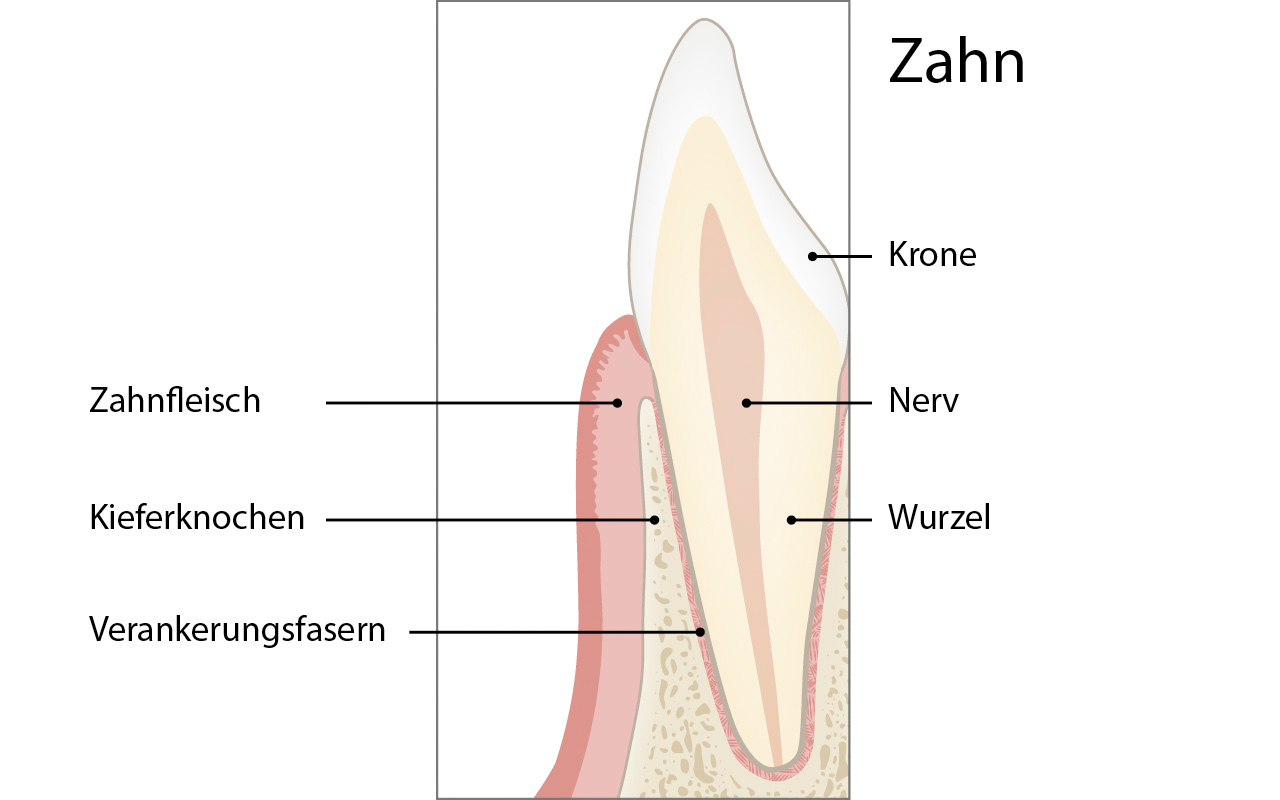

Mehr ...Jeder Zahn besteht aus einer Krone, einer Wurzel und einem Nerven. Der Zahn ist an seiner Wurzeloberfläche mit Verankerungsfasern im Zahnfleisch und im Kieferknochen befestigt.

Wie ist der Zahn im Kieferknochen verankert?

Jeder Zahn besteht aus einer Krone, einer Wurzel und einem Nerven. Der Zahn ist an seiner Wurzeloberfläche mit Verankerungsfasern im Zahnfleisch und im Kieferknochen befestigt.

Die Zahnkrone ist von Zahnschmelz (Schmelz) überzogen. Darunter befindet sich das Zahnbein (Dentin) und wiederum darunter der Nerv des Zahnes (Pulpa). Genaugenommen besteht die Pulpa aus dem Nerv, den Blutgefässen and einem sogenannten Bindegewebe. Während der Schmelz ohne Nerven und daher ohne Empfindung ist, wird das darunter gelegene Dentin von Nervenfasern versorgt. Die Oberfläche der Zahnwurzel ist daher auch schmerzempfindlich.

Das Zahnbein (Dentin) macht den Hauptbestandteil der Wurzel aus. Die Wurzel wird zusätzlich von einer harten Schicht, der sogenannten Wurzelhaut (Wurzelzement) überzogen. Der Zahn ist entlang seiner gesamten Wurzeloberfläche mit Verankerungsfasern (Desmodontalfasern) im Kieferknochen befestigt. Diese Fasern sind einerseits im Wurzeldentin und andererseits im Kieferknochen verankert.

Die Zahnwurzel ist länger als die Zahnkrone. Insbesondere haben die Eckzähne im Oberkiefer (Reisszähne) meistens sehr lange Wurzeln.